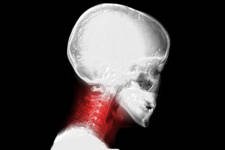

Los dolores a nivel del cuello son frecuentes, nos limitan y nos reducen la calidad de vida. El 66% de las personas sufren de dolor de cuello. Muchas veces este dolor se vuelve crónico con el paso del tiempo.

Con la edad, se produce la degeneración de los discos y de las articulaciones cervicales y se ha comprobado que esta degeneración es causa frecuente de dolor cervical. No es raro que alteraciones a nivel cervical puedan producir dolores de cabeza o incluso vértigo.

El dolor cervical suele localizarse en la parte más posterior del cuello, suele ser un dolor irradiado, principalmente a la zona occipital y a la columna dorsal. No es raro que se irradie al hombro o al oído. Incluso algunas cefaleas o mareos pueden tener su origen a nivel cervical.

Las pruebas diagnósticas como las radiografías o la resonancia no nos aportan demasiada ayuda, a partir de determinada edad aparecen cambios degenerativos, y no es posible simplemente viendo las imágenes encontrar la alteración responsable del dolor, sin embargo existen indicios que nos pueden hacer pensar en un posible origen del dolor.